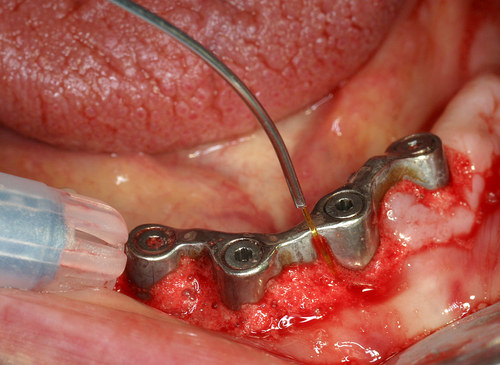

Un rayonnement laser pénétrant utilisé sous eau oxygénée à 10 volumes permet de décontaminer tout l’os du maxillaire après l’extraction des dents (fig. 30)

Fig. 30

Décontamination du maxillaire après extractions